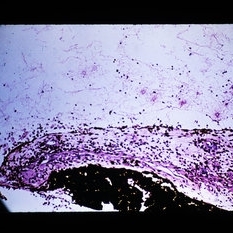

Polymorphonuclear leukocytes (PMNs) marginated around a vein wall and passing into the tissue. Limbal episclera is shown after a penetrating injury. (H&E stain)

Condition/keywords: limbal episclera, polymorphonuclear leukocytes (PMNs)